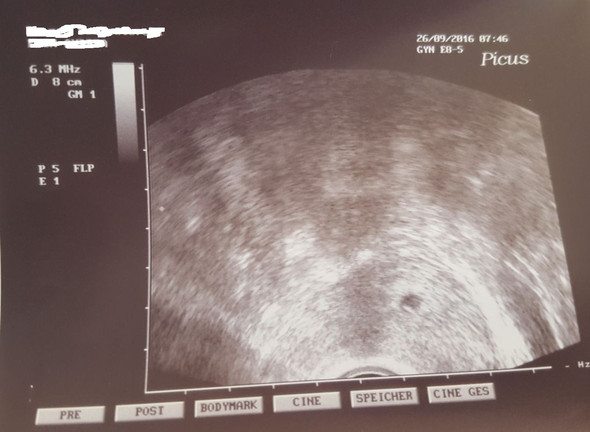

Zusätzlich überprüft er den Beta HcgWert von gestern mit dem des kommenden Montags (165)bitte um Antworten!. Ich befinde mich nun in der 7 ssw Ich weiss von meiner Schwangerschaft erst seit letzten Samstag Nun ist es so, dass ich seitdem braunen Schleim in meiner Einlage bemerkt habe Dh kein braunen ausfluss, der urin ist normal gelb jedoch ist abundzu dieser Schleim leicht am Toilettenpapier Entschuldigt die Derails. (man sieht es etwas rechts im Bild) In der 7 SSW kann man bereits den Herzschlag des Embryos erkennen Der Herzschlag ist ein wichtiger Faktor, an dem man die Entwicklung 7 SSW Herzschlag und Entwicklung.

7ssw baby zu sehn aber kein herzschlag Ehemaliges Mitglied 1518 hallo erstmal ich bin in der 7ssw war am dienstag beim frauenarzt dort war auch das baby zu sehn und der dottersack aber noch kein herzschlag am montag muss ich nochmal hin ,muss ich mir sorgen machen war es bei jemand schon mal so?und kam noch ein herzschlag ?. Guten Abend, ich bin in der Schwangerschaftswoche 72 und hatte heute einen Ultraschall auf dem noch kein Herzschlag zu sehen war Die Größe des Embryos wurde. Embryo zu klein, kein Herzschlag (SSW 71) Hallo ihr Lieben, mir ist heute Morgen mein Herz komplett zerbrochen Zur Vorgeschichte Ich sollte angeblich niemals schwanger werden können, da meine Blutwerte vor 1,5 Jahren anzeigten, dass ich bereits in den Wechseljahren war Daraufhin musste ich ins Kinderwunschzentrum und dabei stellte sich dann heraus,dass ich nicht in den.